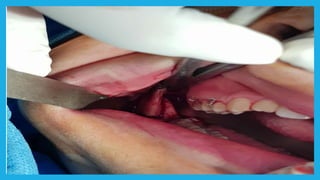

Mandibular segmental procedures Anterior subapical procedure